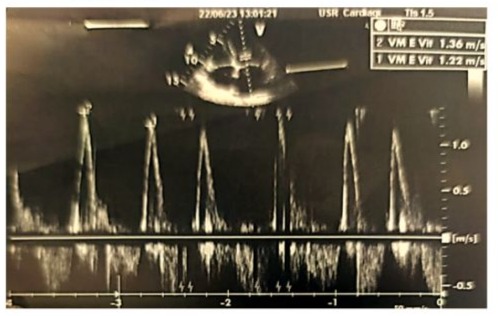

Left ventricular filling pressures were normal, and the inferior vena cava was dilated to 16 mm and slightly compliant. (Figure 3,4) The left atrium was dilated, with a surface area of 21.5 cm² and a volume of 44 ml/m². (Figure 5) The right ventricle had preserved systolic function with a TAPSE (Tricuspid Annular Plane Systolic Excursion) of 22 mm and a tissue Doppler S’ velocity of 12 cm/s. The right atrium was dilated at 19.7 cm², free of echoes. Assessment of the valvular apparatus showed a tricuspid aortic valve with degenerative changes, including calcified masses between the right and left cusps, limiting valve opening. Severe stenosis was noted, with a valvular area of 0.8 cm² (indexed area of 0.58 cm²), a Vmax of 3.93 m/s, and a mean gradient of 35 mmHg. The aortic annulus measured 19 mm, and minimal regurgitation was observed. (Figure 6-9)

Figure 3: Doppler echocardiographic image of the transmitral antegrade flow showing a non-elevated mitral E-wave velocity of 1.36 m/s (<1.5 m/s), with the absence of an A-wave due to atrial fibrillation.